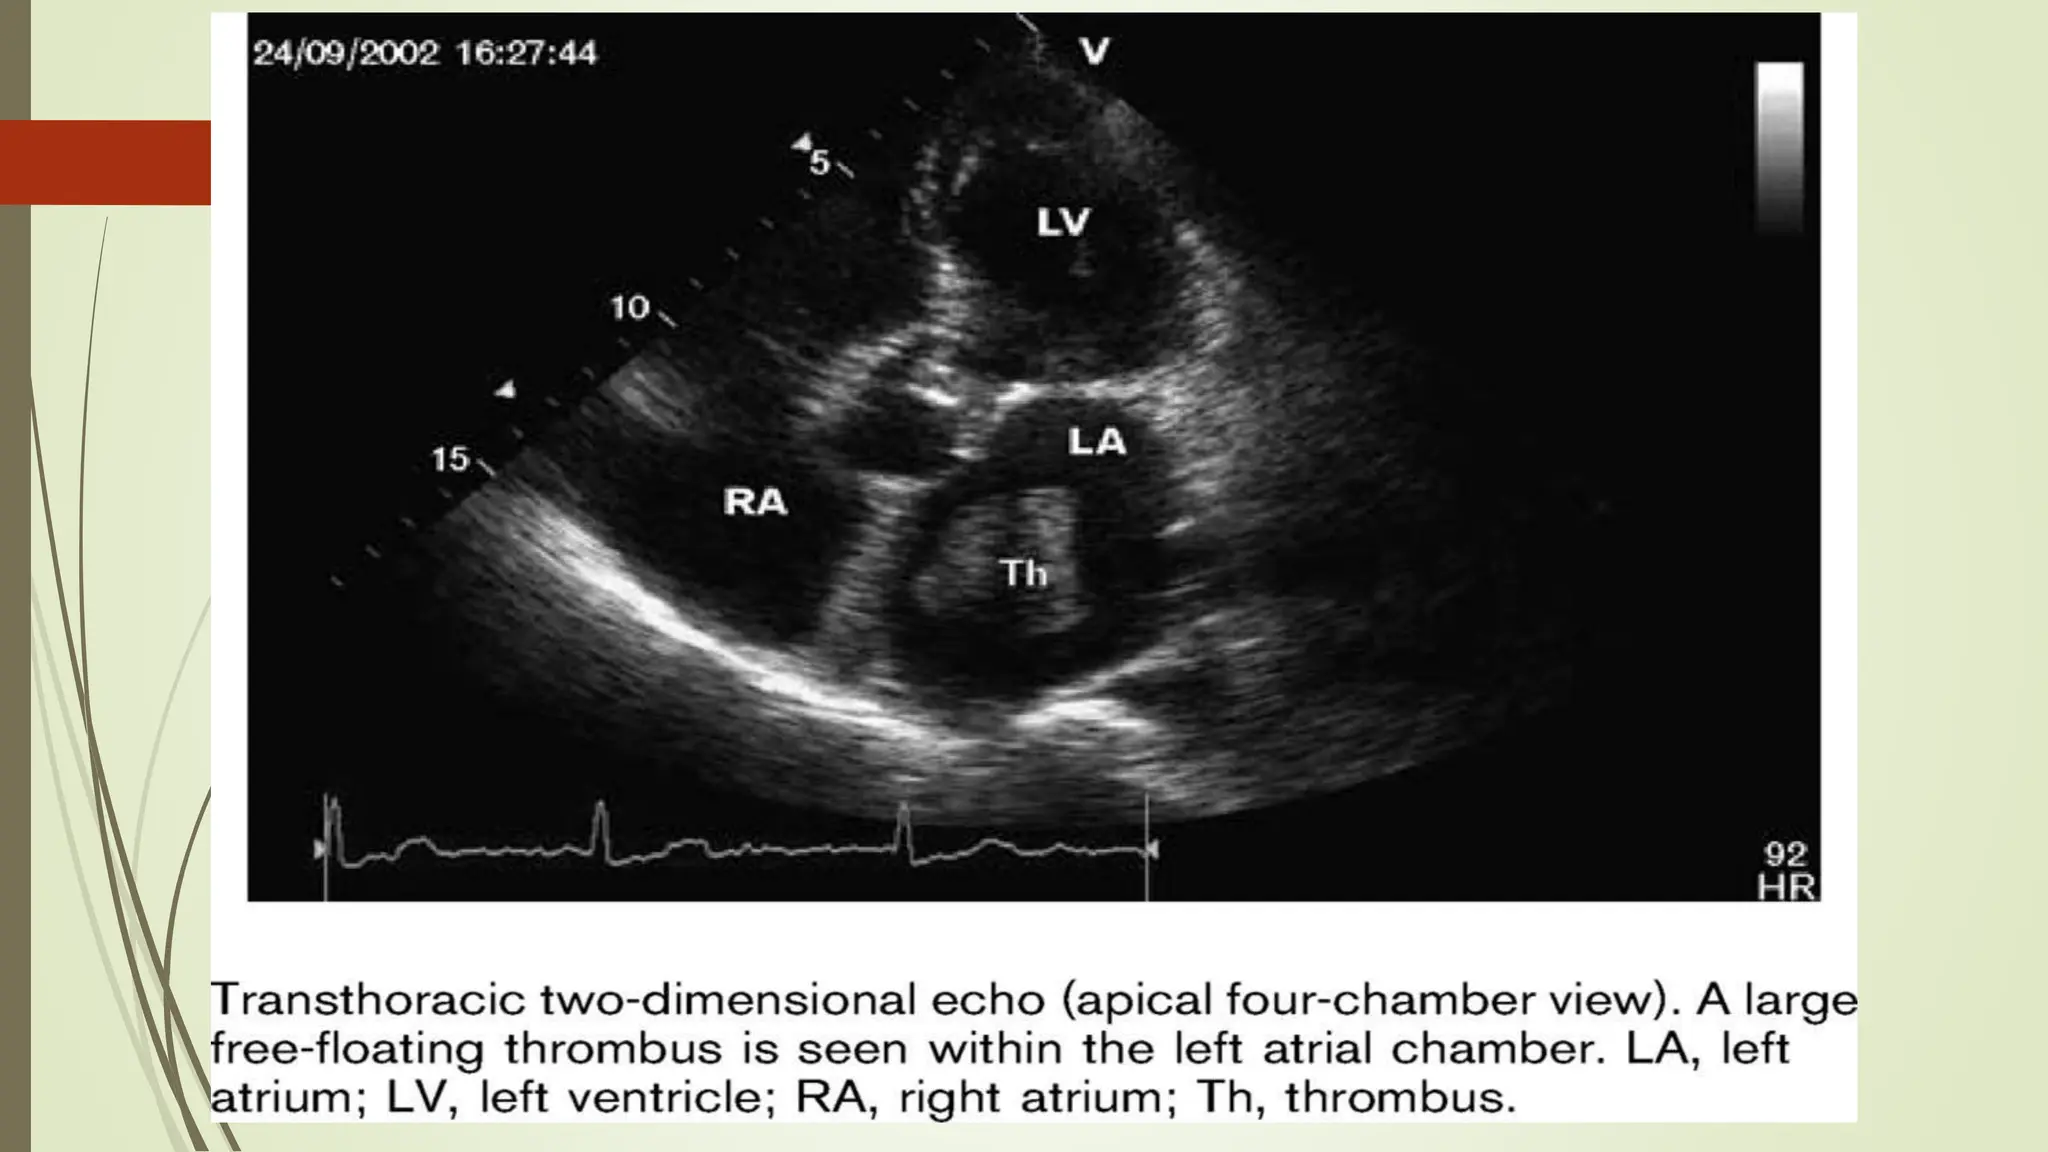

The document discusses various types of atrial flutter, including those with different block patterns such as 2:1, 4:1, and variable blocks, as well as conditions like high-grade AV block and 1:1 block. It also mentions AV nodal reentry tachycardia (AVNRT) and its reversion to sinus rhythm after an adenosine bolus. Additionally, atrial fibrillation is briefly referenced.